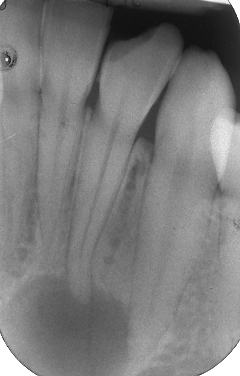

Apertura della corona fino ad arrivare alla camera pulpare (tale trattamento viene eseguito tramite anestesia locale). Si rimuove la polpa e si cercano i canali radicolari del dente, una volta trovati si estirpano i nervi. Si allargano e si puliscono i canali del dente, (tramite strumenti al Nichel titanio o strumenti manuali) prendendo anticipatamente le misure dei canali (per non uscire oltre apice). Si disinfettano i canali e si eseguono vari lavaggi tra un passaggio e un altro per elimininare il fango dentinale. Il medico a questo punto verifica la possibilità di chiudere definivamente i canali o lasciare il dente in prova, inserirendo nei canali un disinfettante e eseguendo una chiusura provvisoria. Al momento di chiudere il dente definivamente, questo viene preparato rieseguendo le misure dei canali da chiudere ed usando per la stessa lunghezza del canale, un cono di guttaperga del diametro necessario. Si scalda il cono in guttaperga e si inserisce nel canale. Durante il trattamento endodondico vengono effettuati una serie di esami radiografici per verificare i risultati, le lunghezze, la forma dei canali.

L'esame radiografico, fondamentale per porre diagnosi in odontoiatria, in endodonzia è irrinunciabile perché è l'unico strumento che ci permette di "vedere" all'interno della radice del dente, è quindi molto importante la possibilità di effettuare lastre con apparecchiature digitali che emettono un quarto della dose di raggi emessa da un radiografico tradizionale e che permettono di conservare la radiografia endorale in una cartella informatica del paziente senza possibili alterazioni nel tempo.